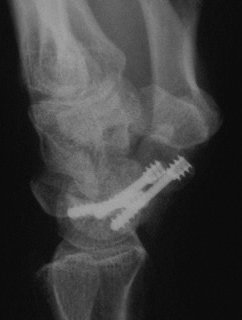

Case 4. Nonunion with a graft and screws placed in both directions from a single palmar approach, hyperextending the wrist for the proximal entry...

Click for larger image

and with the graft:

and with consolidation,